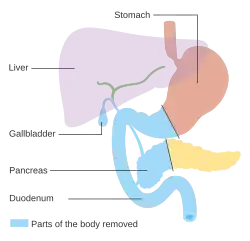

Nos cancros que envolvem a cabeça do pâncreas, o procedimento de Whipple é o tratamento cirúrgico curativo mais comum. Esta operação consiste na remoção em simultâneo da cabeça do pâncreas e da curva do dudodeno ("duodenopancreatectomia"), na criação de um bypass para os alimentos desde o estômago até ao jejuno ("gastro-jejunostomia") e na ligação do jejuno ao ducto cístico para drenar a bílis ("colecisto-jejunostomia"). Este procedimento só pode ser realizado caso a pessoa tenha condições de sobreviver a uma intervenção cirúrgica de risco e quando o cancro não invade estruturas locais ou apresenta metástases, pelo que só é possível numa minoria de casos. Os cancros da cauda do pâncreas podem ser removidos através de um procedimento denominado pancreatectomia distal, que em muitos casos implica também a remoção do baço.[2][3] Hoje em dia, este procedimento pode ser feito através de métodos minimamente invasivos.[2][3]